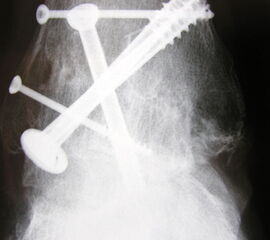

Fixation mit mindestens 2, ggf. 3 kanülierten Schrauben (6,0, 6,5 oder 7,0 mm), die von medial-kranial und lateral-kranial nach kaudal oder von anterior-kranial nach posterior-distal (Abb. 6) in den Talus unter BV-Kontrolle in 2 Ebenen eingebracht werden (Sabo 2014). Im amerikanischen Sprachraum ist die Verwendung der von dorsal-lateral paraachillär nach anterior-medial in den Corpus tali gerichteten Zugschraube geläufig („home run-screw“) (Abb. 7). Es ist darauf zu achten, das untere Sprunggelenk nicht mit Schrauben zu perforieren. Idealerweise spannen die Kompressionsschrauben, deren Gewindegänge nur im Talus liegen sollten diesen stabil in die Malleolengabel ein.

Abbildung 7